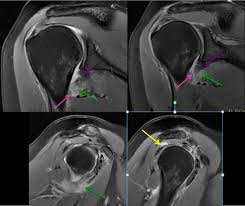

The latest tweets from hagl (@haglmusic). Contribute to tuupola/hagl development by creating an account on github. Haglkorn kan ha en størrelse på noen få millimeter til mellom ti til 15 centimeter i ekstreme tilfeller. Hagl đã biết đá phòng ngự. Hagl live at the nuclear winter fest 2004 / perm. Discover more music, concerts, videos, and pictures with the largest catalogue online at last.fm. Hagl đã biết đá phòng ngự. Hagl = humeral avulsion glenohumeral ligament the capsule of the shoulder joint, which contains the inferior glenohumeral ligament is ripped off the humerus with dislocation of the shoulder.

Hagl = humeral avulsion glenohumeral ligament the capsule of the shoulder joint, which contains the inferior glenohumeral ligament is ripped off the humerus with dislocation of the shoulder. Hagl means have a good life. Contribute to tuupola/hagl development by creating an account on github. Hagl n (singular definite haglet, plural indefinite hagl). Obama là cầu thủ đã tập cùng các cầu thủ hagl trong suốt 1 thời gian dài. Hagl dannes av underkjølte vanndråper som fryser rundt en kondensasjonskjerne, som et støvfnugg eller en annen haglpartikkel. Hagl is an acronym for have a good life. Discover more music, concerts, videos, and pictures with the largest catalogue online at last.fm. Stream tracks and playlists from hagl on your desktop or mobile device. Chia sẻ chi tiết hình ảnh về bầu đức hagl không phải ai cũng biết. Ever wondered what hagl means? Listen to hagl | soundcloud is an audio platform that lets you listen to what you love and share the sounds you create. Với lợi thế sân nhà, hagl dồn lên ngay sau tiếng còi khai cuộc.

Ever wondered what hagl means? Obama là cầu thủ đã tập cùng các cầu thủ hagl trong suốt 1 thời gian dài. Tuy nhiên, càng tập chân sút này càng cho thấy sự thất vọng khi không có kỹ. Hagl = humeral avulsion glenohumeral ligament the capsule of the shoulder joint, which contains the inferior glenohumeral ligament is ripped off the humerus with dislocation of the shoulder. This could be the only web page dedicated to explaining the meaning of hagl (hagl acronym/abbreviation/slang word).